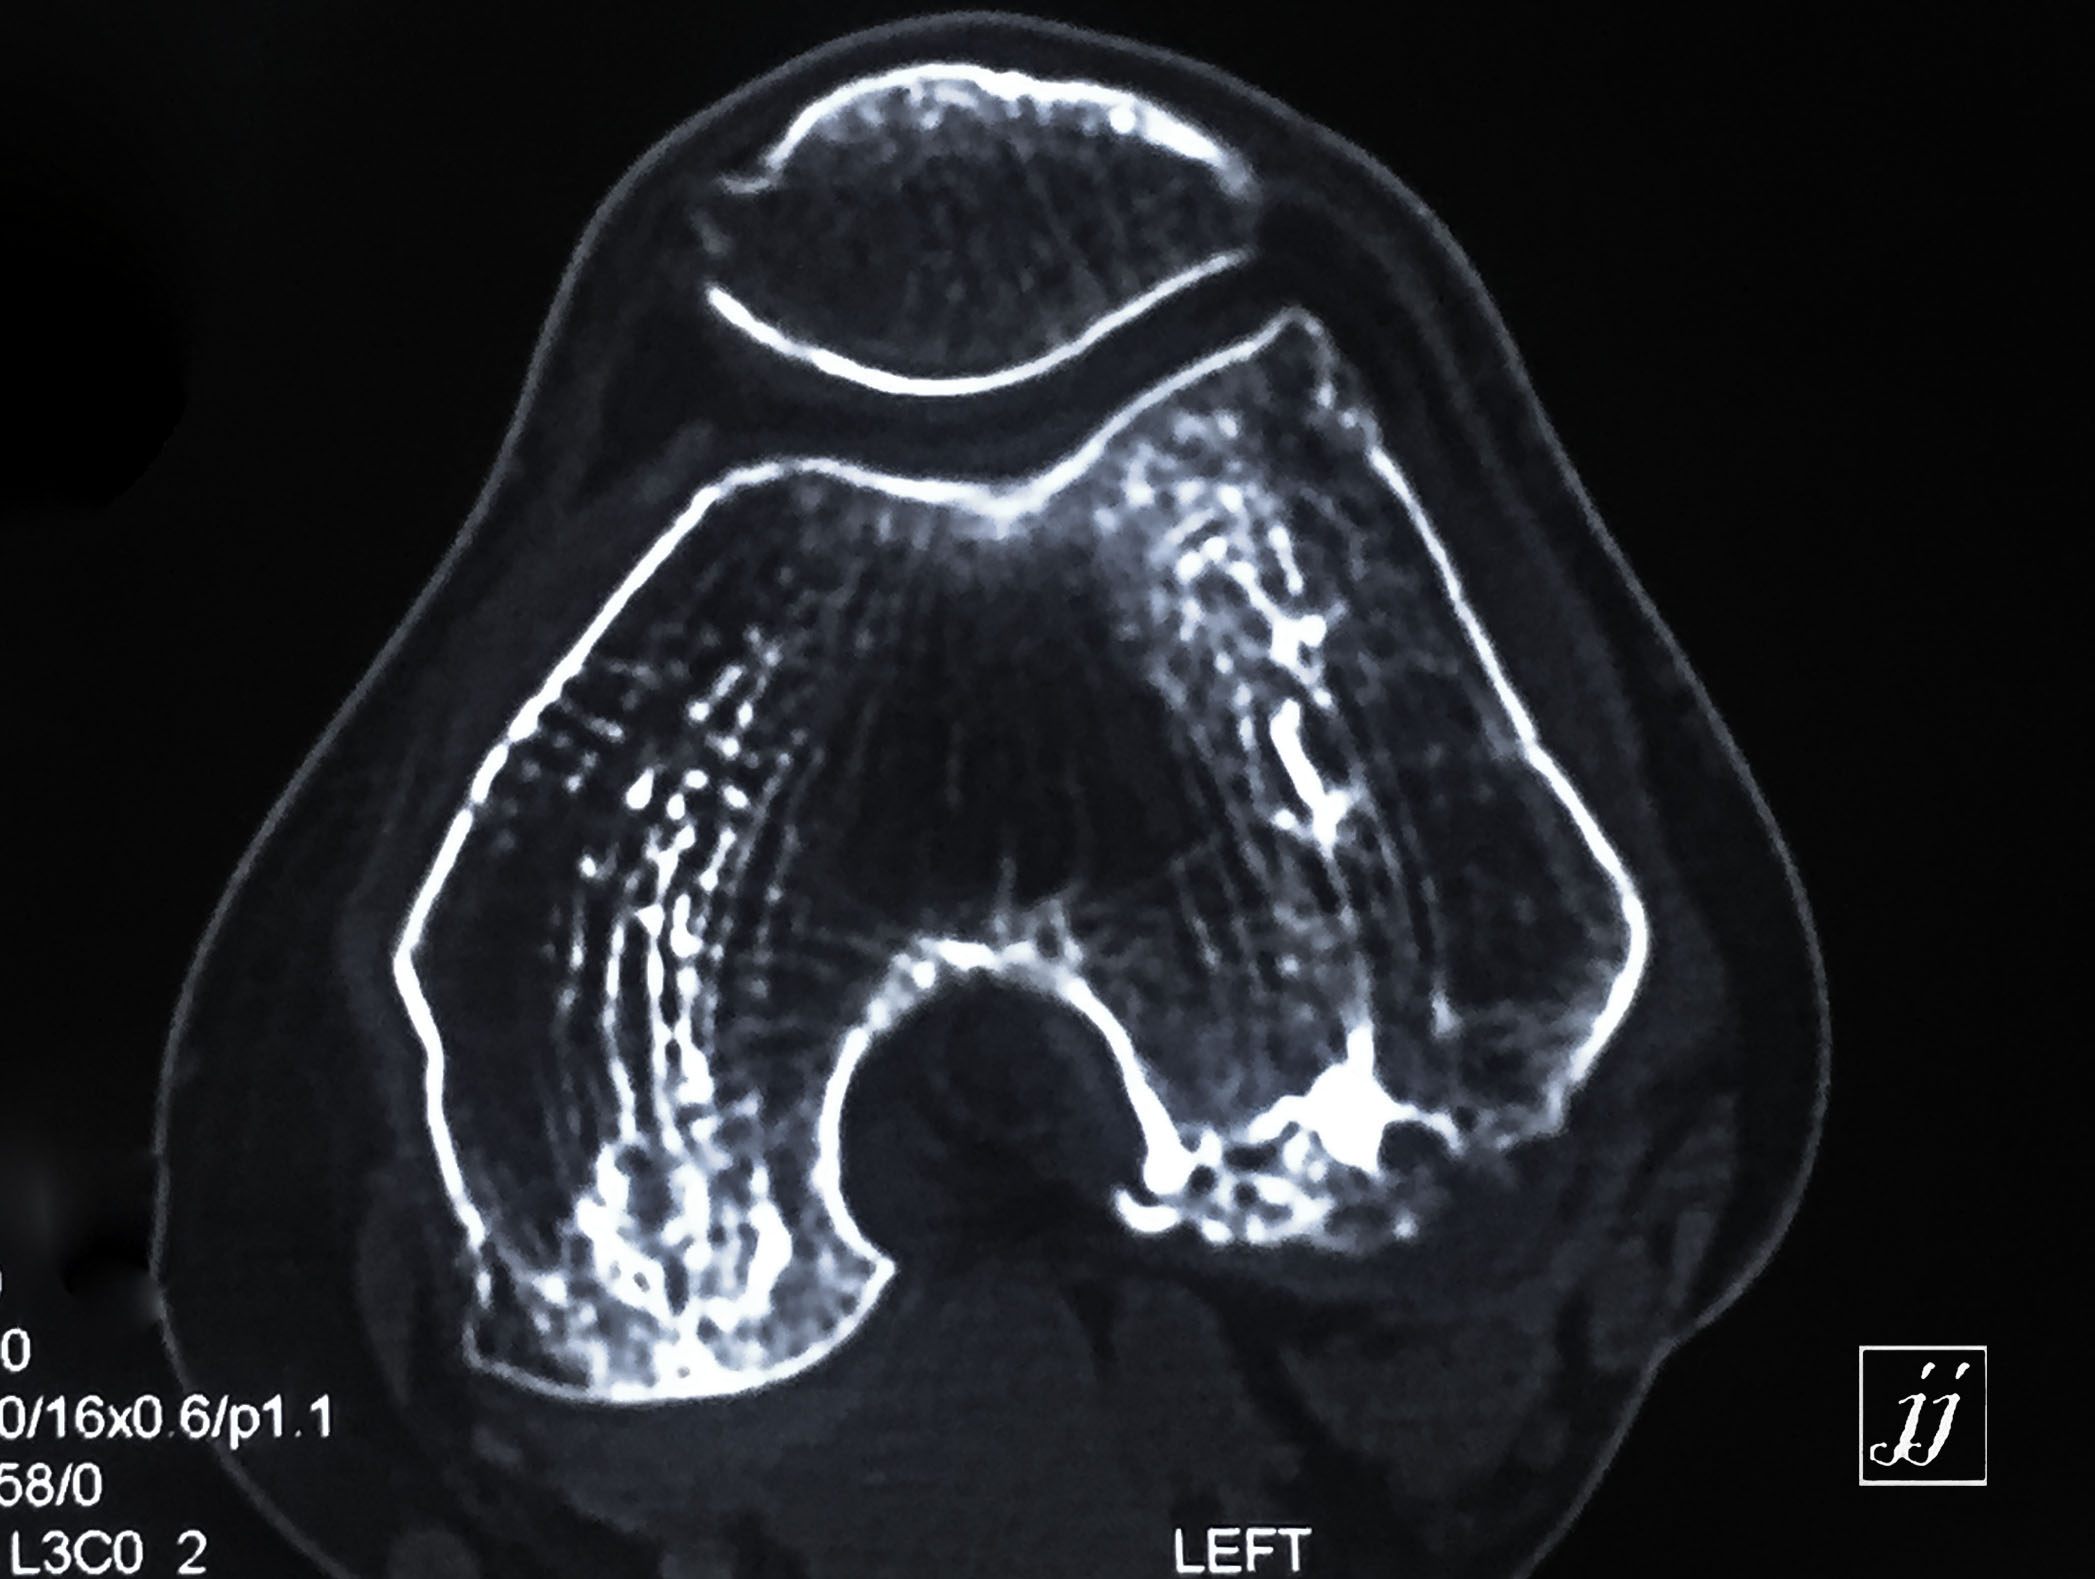

MSK- proximal tibia fracture and infection (26)